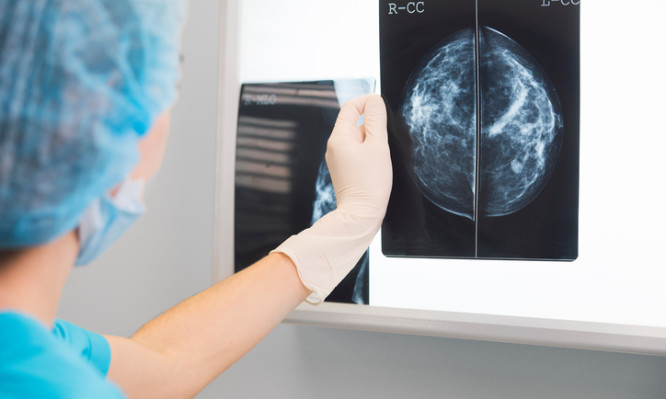

Σημαντική η ετήσια, ισόβια μαστογραφία μετά τα 40 χρόνια

«Κάθε γυναίκα που είναι υγιής και θέλει να παραμείνει υγιής πρέπει να κάνει μαστογραφία σε όλη της τη ζωή ξεκινώντας από την ηλικία των 40 ετών, (αν δεν υπάρχει ατομικό ή οικογενειακό ιστορικό) με δεδομένο όμως ότι η ετήσια εξέταση των μαστών, ο υπερηχοτομογραφικός έλεγχος και η κλινική εξέταση θα πρέπει να ξεκινούν από την ηλικία των 20 ετών» τονίζει σε δηλώσεις της η Ιατρός Ακτινοδιαγνώστης Μαρία Χριστοδούλου, συνιδιοκτήτης του Διαγνωστικού Κέντρου ‘’Απεικόνιση Αιγαίου’’ που δραστηριοποιείται στην περιοχή των Δωδεκανήσων, με έδρα τη Ρόδο.

Οι γυναίκες ανεξαρτήτως ηλικίας δεν θα πρέπει να εκδηλώνουν άγχος ή ακόμη και πανικό, εάν στην τυχαία ψηλάφηση του μαστού τους εντοπίσουν κάποιο εξόγκωμα, γιατί αυτό μπορεί να είναι αθώο και χωρίς καμία σημασία, δεδομένου ότι ο καρκίνος δεν είναι το μόνο εύρημα που διαγιγνώσκεται κάνοντας προληπτικό έλεγχο.

«Υπάρχουν και πολλά καλοήθη ευρήματα στους μαστούς που δεν είναι απαραίτητο να δίνουν συμπτώματα, γνωρίζοντας όμως την ύπαρξή τους, αυτά μπορεί να θεραπευτούν έγκαιρα και να μειωθούν οι πιθανότητες που διατρέχει μια γυναίκα να νοσήσει από καρκίνο του μαστού», προσθέτει η κ. Χριστοδούλου.

Ιδιαίτερης σημασίας για κάθε γυναίκα, είναι να μην αποφασίζει μόνη της για τον προληπτικό έλεγχο που πρέπει να κάνει, αλλά αυτό να της προταθεί από τον κλινικό ιατρό που θα της συστήσει το δικό της ατομικό πρωτόκολλο παρακολούθησης. Ο σκοπός είναι διττός, αφενός μεν η όσο το δυνατόν έγκαιρη διάγνωση του καρκίνου του μαστού, αφετέρου δε η μείωση των πιθανών προδιαθεσικών παραγόντων, όπως το κάπνισμα, το αλκοόλ κλπ.

«Η προσωπική επαφή με το ιατρό», καταλήγει η κ. Χριστοδούλου, είναι απαραίτητη και έχει αποδειχθεί ότι βελτιώνει τη διαγνωστική προσέγγιση της ασθενούς, μειώνοντας τα απεικονιστικά λάθη που ενδεχόμενα μπορεί να συμβούν, χωρίς ενδελεχή έλεγχο του ιστορικού της».